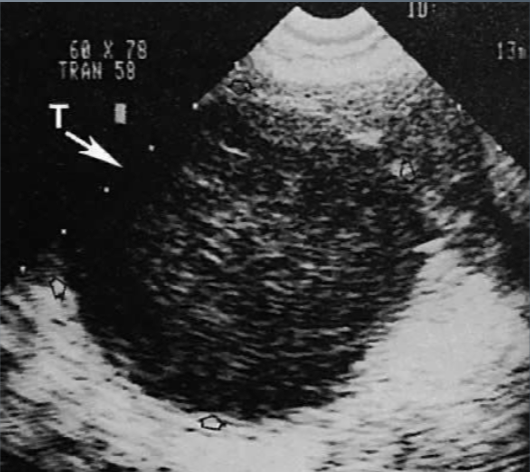

Benign Cystic Teratoma

Most common germ cell tumor of the pelvis

Most frequently visualized ovarian tumor in women under 20

Made from same germ cell layers that make up hair, skin, glandular tissues, bone, and fat

malignancy is rare

Benign Cystic Teratoma U/S appearance:

varies

cystic mass

complex mass w/ calcifications

fat-fluid level within complex mass

diffusely echogenic mass w/o shadowing

predominantly solid with echogenic foci that represent calcium or fat with or without shadowing

“Tip of the Iceberg”